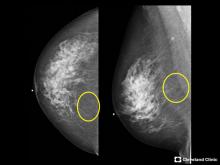

VIDEO: COVID Vaccine May Cause Enlarged Lymph Nodes on Mammograms — Interview with Constance "Connie" Lehman, M.D.

COVID-19 Vaccination Axillary Adenopathy Detected During Breast Imaging